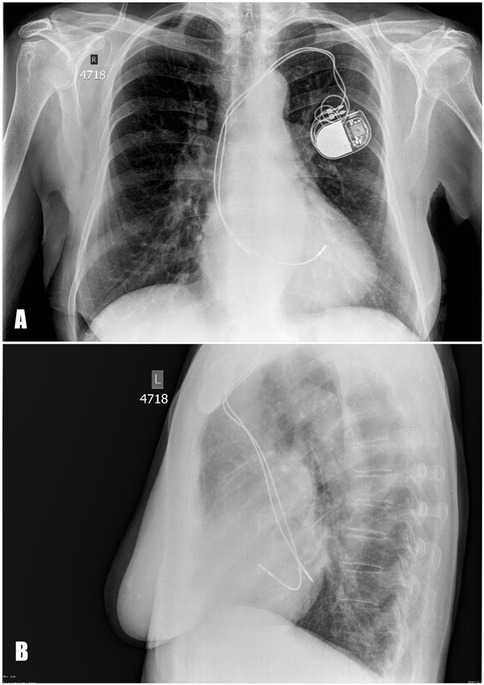

A blood test revealed an elevated level of NT-proBNP 502 pg/mL. The chest x-ray demonstrated that the pacing lead followed an atypical course (Figure 1). TTE showed abnormal lead positioning, dilatation of right heart chambers, and moderate tricuspid regurgitation.

Figure 1

Posteroanterior (А) and lateral (B) chest x-ray. The pacing leads are abnormally positioned, suggesting placement in the left heart instead of the right.